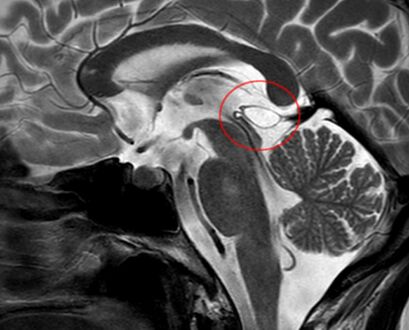

The National Organization for Rare Disorders states that pineal cysts larger than 5.0 mm are "rare findings" and are possibly symptomatic. If narrowing of the cerebral aqueduct occurs, many neurological symptoms may exist, including headaches, vertigo, nausea, muscle fasciculations, eye sensitivity, and ataxia. Continued monitoring of the cyst might be recommended to monitor its growth, and surgery may be necessary.[3]